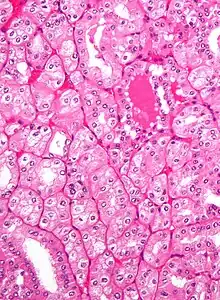

Micrograph of a renal oncocytoma. H&E stain.

An oncocytoma is an epithelial tumor composed of oncocytes, large eosinophilic cells having small, round, benign-appearing nuclei with large nucleoli and excessive amounts of mitochondria.